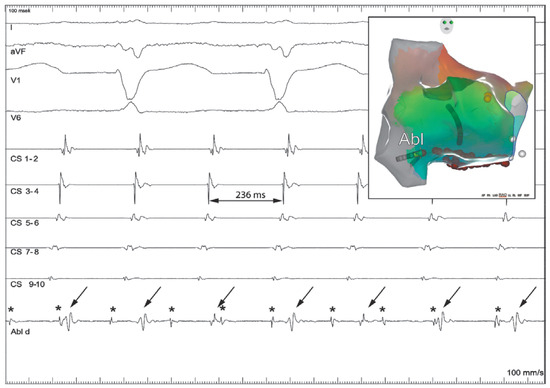

The Eustachian ridge is ablated as part of the cavotricuspid isthmus (CTI) involved in typical atrial flutter (AFL) ablation, but is itself rarely an arrhythmogenic focus. We report a case of a patient with dual tachycardia involving the CTI area....